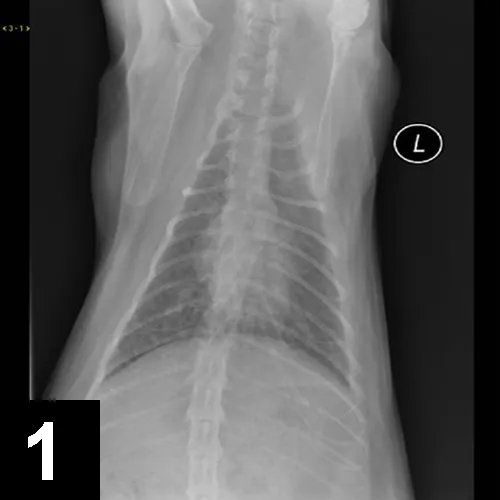

Luna was placed in an oxygen-enriched cage, and thoracic radiographs (Figure 1) were taken.

Figure 1. Thoracic radiographs taken at presentation.

Luna’s clinical signs and radiograph findings were most consistent with lower airway disease (ie, feline asthma). While asthma implies reversible bronchoconstriction, some cats with lower airway disease have more inflammatory changes and less reversible airway changes.

Radiographic findings consistent with airway disease include donuts and tram lines, which are supportive of bronchial thickening and hyper­inflation from expiratory flow limitation. Some cats with lower airway disease also have a collapsed middle lung lobe (Figure 2).